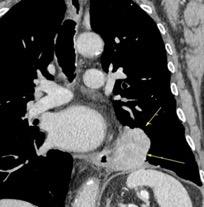

Aneurisma roto

Neurofibromatosis 1

1/ Bhalla S et al. CT of Nontraumatic Thoracic Aortic Emergencies. Semin Ultrasound CT MRI. 2005/ Zeiler J et al. Hemothorax: A review of literature. Clin Pulm Med. 2020 .

Hematoma pleural después de cateterismo.

Rotura de aneurisma de arteria subclavia Aneurisma “deshinchado” Hemotórax

Fallece en el acto de tomar esta radiografía. La mayoría ateroescleróticos. Más frecuente a la derecha.La rotura: 32-47% de las muertes.

Sun J et al. Isolated True Subclavian Aneurysm without Aberrant Subclavian Artery or Coarctation of Descending Aorta. Annals of Vascular Surgery 2021

Johansson G, et al. Ruptured thoracic aortic aneurysms: a study of incidence and mortality rates. J Vasc. Surg. 1995;